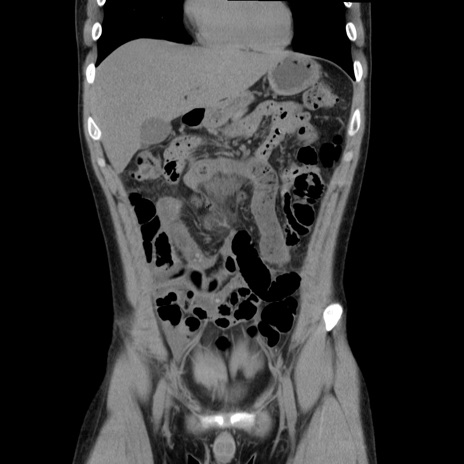

症例36(冠状断像)

【症例】20歳代 男性

【主訴】心窩部痛

【現病歴】今朝より上腹部痛あり。一旦軽快していたが再度出現したため救急要請。昨日夕に白身の魚を含む刺身を食べた。

【身体所見】BP 136/89mmHg、HR 74/min、BT 37.0℃、腹部:膨満、軟、心窩部に圧痛あり。反跳痛なし、筋性防御なし、腸雑音やや亢進あり。

【データ】WBC 17700、CRP 0.48